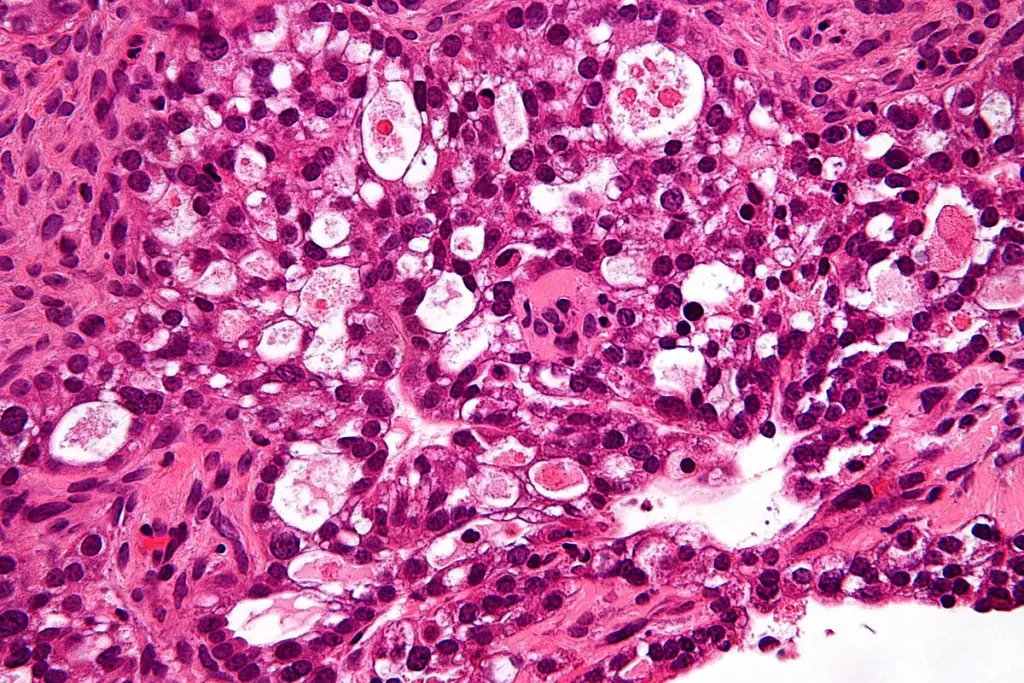

A precise cancer diagnosis is essential for creating an effective treatment plan. The process begins with a physical exam and a review of medical history. While imaging tests like CT scans, MRIs, and PET scans provide images of a tumor’s size and location, a biopsy is the definitive diagnostic tool. This involves removing a small tissue sample for a pathologist to examine. Blood tests may also be used to detect tumor markers. This collective data is then used to “stage” the cancer, a critical step that determines the extent of the disease.

When a symptom suggests cancer, a doctor will begin with a thorough physical exam and a review of medical history. If a specific area is suspected, the next step is typically an imaging test to visualize the inside of the body. However, cancer can only be confirmed with a biopsy. This procedure involves a specialist (such as a surgeon or radiologist) taking a sample of the suspicious tissue. A pathologist then analyzes these cells under a microscope to confirm the presence of cancer and identify its specific type.